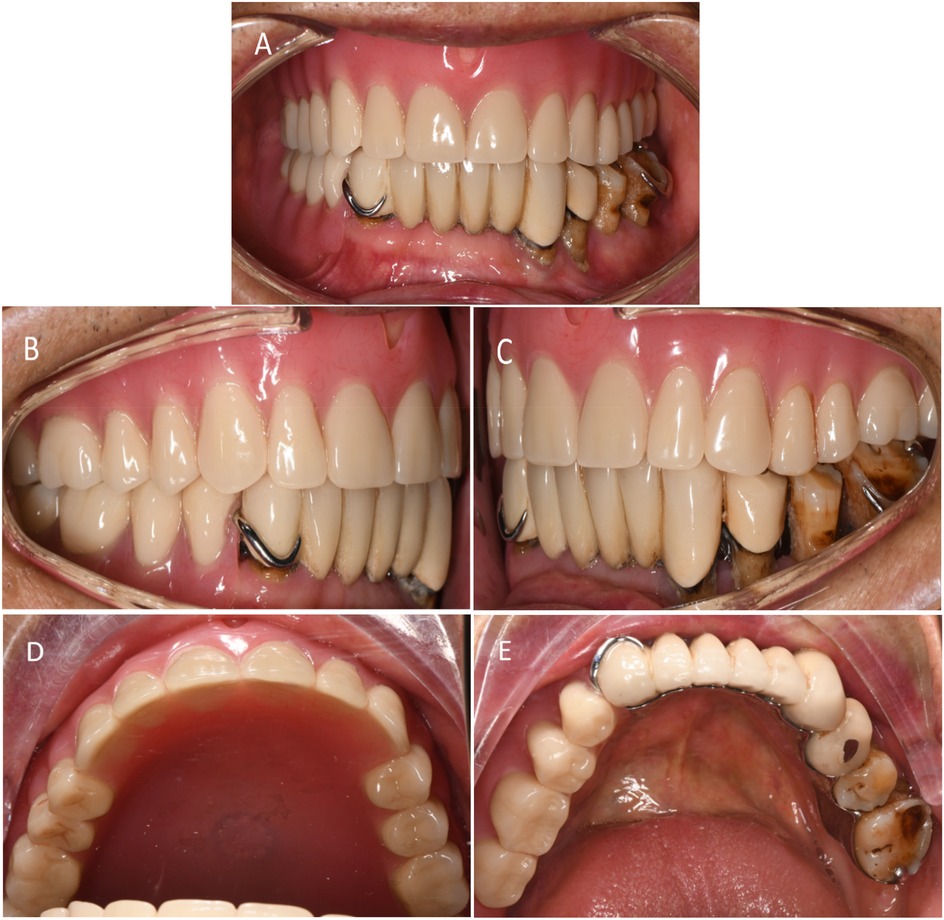

5. Initial denture placement and professional guidance: The position and retention of the denture were evaluated, checking for any lifting or tenderness, whether the base edge is excessively long, and if the frenulum buffer is adequate. Additionally, the patient's facial profile was assessed, ensuring that the vertical dimension was appropriate, jaw relationship was correct, and that the denture achieved balanced occlusion (Figures 1-bottom, 6, and 7). The use of dentures should be restricted due to the adhesion and negative pressure exerted on the palatal mucosa by the suction cup. The patient was advised to wear them only while eating and chewing, using the right side for these activities. Furthermore, close attention was paid to palatal mucosal conditions.

Figure 7. Postoperative photographs. (A) Buccal view of denture. (B) Right-side occlusion (non-defect side). (C) Left-side occlusion (defect side). (D) Occlusal view of the maxillary denture. (E) Occlusal view of the mandibular denture.